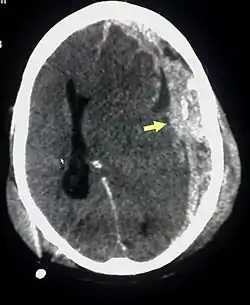

![]() ورم دموي تحت الجافية (مشار له بالسهم)، النزف بين الأم الجافية للسحايا والدماغ يحدث عادة في متلازمة الرضيع المهزوز. ورم دموي تحت الجافية (مشار له بالسهم)، النزف بين الأم الجافية للسحايا والدماغ يحدث عادة في متلازمة الرضيع المهزوز. | |

الإصابات المميزة المرتبطة بمتلازمة الرضيع المهزوز التي من ضمنها نزيف في شبكية العين وكسور متعددة في العظام الطويلة وورم دموي تحت الجافية (نزيف في الدماغ). وقد تطورت هذه العلامات على مر السنين كعلامات متعارف عليها لإساءة معاملة الأطفال متلازمة الرضيع المهزوز. اخصائيين الطب يشتبهون وبقوة أن الهز هو السبب في إصابة الطفل الرضيع أو الطفل الصغير بنزيف في شبكية العين وكسور وإصابة الأنسجة اللينة أو ورم دموي تحت الجافية، والتي لا يمكن تفسيرها من خلال الصدمات العرضية أو الحالات الطبية الأخرى. نزيف شبكية العين يحدث في حوالي 85% من حالات متلازمة هز الطفل. نوع النزيف في شبكية العين يعتبر ميزه مفيدة جداً في تحديد التشخيص، حيث أن هناك العديد من الأسباب الأخرى لنزيف شبكية العين غير متلازمة الرضيع المهزوز، وعادة ما تكون هناك نتائج إضافية (عينية و/أو المنهجية) التي تجعل التشخيصات الأخرى واضحة. كسر الفقرات والعظام الطويلة والضلوع قد تكون ايضاً مرتبطة بمتلازمة الرضيع المهزوز. كما أفاد الدكتور جون كافي في عام 1972 ان الأفولسيونس ميتافيزيل (وهي شظايا صغيرة من العظام قد يمزق فيها السِمحاق وهي جلدة أو قشرة رقيقة تغطي عظم الرأس والعظام القشرية) وذلك يؤثر على العظام بشكل عام سواء كانت العظام القريبة والبعيدة من الرأس " كعظام الركبة خاصة". ومن الأثار الشائعة ايضا بسبب متلازمة الرضيع المهزوز إصابة المحور العصبي، وعدم وصول الأكسجين وتورم الدماغ، وهذا قد يؤدي ايضا لارتفاع الضغط داخل الجمجمة وتلف الأنسجة الحساسة في المخ. والمصابين بمتلازمة الرضيع المهزوز قد يعانون من التهيج، وفشل بالنمو، واضطرابات في أنماط الأكل والشعور بالخمول والتقيؤ والشعور بنوبه واليافوخ اأو المنتفخه وهي (بقع ناعمة تظهرعلى رأس الرضيع)، وزيادة في حجم الرأس، وصعوبات في التنفس، وإتساع في حدقة العين .

الثالوث :وغالباً ما يشار على أنه "ثالوث". وكفرضية، تم الإشارة إليه على أنه عملية استنتاج العنيف أو مسيئة اهتزاز من النتائج السريرية في تشخيص متلازمة هز الطفل لكفرضية. وفي عام 2000، لخص نائب مدير المركز الوطني للمتلازمة الرضيع المهزوز روب باريش، الـ"ثالوث" على النحو التالي: غالبا ما يشار إليها باسم "ثالوث"، تم الإجماع على انها عبارة عن مجموعه من (1)تلف في خلايا المخ، حيث يتضح ذلك من خلال تورم حاد في الدماغ و/ أو انتشار إصابة المحور العصبي (ضرر يحدث على نطاق واسع ويصيب أكثر من منطقة في الدماغ). (2) نزيف تحت الأغشية التي تغطي الدماغ، مثل نزيف تحت الجافية و/ أو نزيف تحت العنكبوتية (المنطقة الواقعة تحت الغشاء العنكبوتي والغشاء الرقيق الذي يغلف المخ). و، (3) نزيف في طبقات شبكية العين، وايضاً غالباً ما يرافقه اضرار أخرى بالعين.